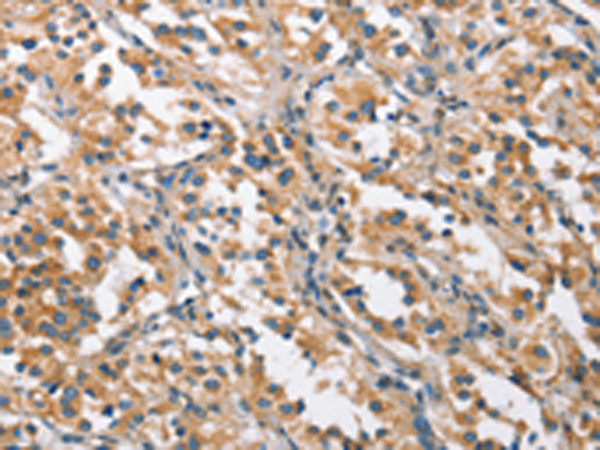

分类: 科研抗体货号: P08178别名: RBP6; CRABP-II应用: IHC反应种属: Human, Mouse, Rat